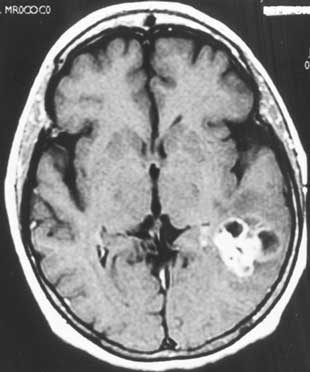

Korábbi állatkísérletek pozitív eredményeit igazolta az a madridi kutatás, amely szerint a THC képes megfékezni az agydaganatok legagresszívabb, legrosszindulatúbb típusának, a gliobastoma multiformé-nak (GBM) a terjedését. A madridi Complutense Egyetem kutatói intratumorális THC injekciókat adtak olyan pácienseknek, akik korábban nem reagáltak a hagyományos kezelési módszerekre (sebészeti beavatkozás vagy kemoterápia). A páciensek közül kettőnél jelentős csökkenést tapasztaltak a tumorsejtek burjánzásában. A kutatók nem nyilvánítottak véleményt abban a kérdésben, vajon a kannabisz pozitívan befolyásolta-e a páciensek túlélési esélyeit, mindenesetre a két személy egy évvel élte túl a terápiát (az átlagos túlélési idő a GBM betegeknél diagnózis után legfeljebb hat-tizenkét hónap). A frissen diagnosztizált betegek ennél jobban reagálhatnak a kezelésre.

„A gliobastoma multiforme a gliomák legrosszabb indulatú típusa, igen agresszív, gyorsan növekedő, legkevésbé differenciált, változatos megjelenésű és terápiásan nehezen befolyásolható daganat. A gliomák több mint fele ilyen daganat. Bármely életkorban jelentkezhet, de 35-45 éveseknél a leggyakoribb. Előfordul, amikor a glioma kezdettől ilyen rosszindulatú formában lép fel, gyakrabban viszont a jobb indulatú gliomákból fokozatosan alakul ki ez a típus. Rendszerint a nagyféltekében, leginkább a homloklebenyben keletkezik. Az agyban elhalások, bevérzések láthatók. Sajnos a beteg életkilátásai a leírtakból eredendően nem jók. E daganatféleség a jelenleg elérhető onkológiai kezelési módok kombinált alkalmazásával sem igazán befolyásolható.”